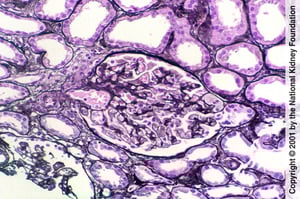

Das obere Bild zeigt die rechte Seite des Glomerulus. Der Glomerulus, der segmental sklerotisch ist, besteht aus verödeten Kapillarlumina und einer erhöhten Menge an Mesangialmatrix. Der Rest des Glomerulus ist normal (Jones-Silberfärbung, ×400). Im unteren Bild ist Hyalin, definiert als glattes, glasig aussehendes Material (das Gegenteil von Exsudation), das aus der Insudation von Plasmaproteinen resultiert. Sie tritt häufig auf und ist nicht diagnostisch (Jones-Silberfärbung, ×400).

Das obere Bild zeigt die rechte Seite des Glomerulus. Der Glomerulus, der segmental sklerotisch ist, besteht aus veröde

Der zentrale Glomerulus in dieser Biopsieprobe weist eine globale Sklerose auf. Der Befund ist unspezifisch und kann sich als Reaktion auf Verletzungen oder Alterung entwickeln (Jones-Silberfärbung, ×100).

Der zentrale Glomerulus in dieser Biopsieprobe weist eine globale Sklerose auf. Der Befund ist unspezifisch und kann si